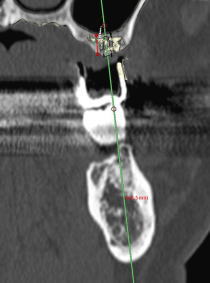

гŽÒ‚³‚ñ‚Ì‚RD—§‘Ì‘œ‚ŃCƒ“ƒvƒ‰ƒ“ƒg‚̃Vƒ…ƒ~ƒŒ[ƒVƒ‡ƒ“‚ð‚µ‚Ü‚·BiŒ©Ï‚à‚è–³—¿j